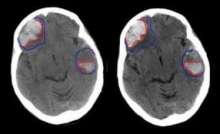

این تحقیقات از جهشی در ژن COL4a2 پرده برداشت که موجب خونریزی در مغز می شود.

اکنون دانشمندان برای نخستین بار کشف کرده اند که انباشته شدن این پروتئین جهش یافته درون سلول ها می تواند موجب سکته مغزی ناشی از خونریزی شود.

دکتر تام ون آگتمل از موسسه علوم پزشکی و قلب و عروق دانشگاه گلاسکو و مجری این تحقیقات می گوید سکته ناشی از خونریزی مغزی نیمی از تمامی سکته های مغزی را در کودکان تشکیل می دهد که در حال حاضر هیچ درمانی برای آن وجود ندارد.